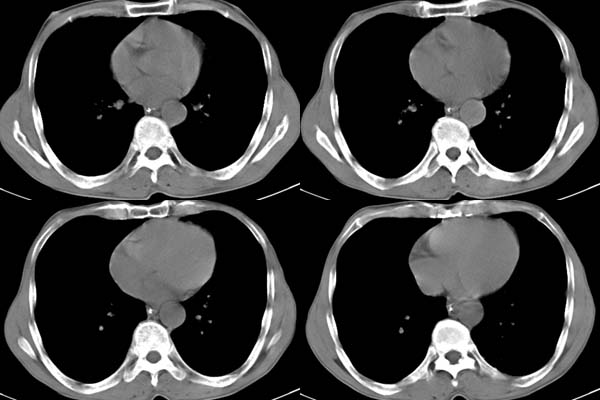

胸膜下见多个软组织结节且以宽基底与胸膜相连,上部肋骨似见骨质破坏,考虑:恶性胸膜间皮瘤。

影像表现不再赘述,支持周围型肺癌,伴胸膜转移。排除胸膜原发肿瘤。

说肺癌纵隔窗上不典型,而胸膜间皮瘤却又没胸水。我觉得胸膜间皮瘤放第一位。

左肺下叶周围型肺癌合并左侧胸膜转移

ct所见:左肺上、下叶近胸膜肺外带可见多个大小不等的结节灶,边界清楚,边缘比较光整。近胸膜病灶似与胸膜以宽基底紧连。提供的病史比较简单,我考虑:1、胸膜原发肿瘤可能性大(就形态来看恶性可能性不大);那么大胆的设想一下,左下叶结节是否与它有必然的联系呢?也可以是结核或周围型肺癌。2、还可以考虑为胸膜和肺内的都是转移灶,病人65岁,是不是其他部位的恶性肿瘤转移过来的呢?因为病灶比较表浅,但一侧发病较少见。3、周围型肺癌并胸膜转移的可能性比较小,一是肺内病灶较小,单发,胸膜结节相对较多,位置较远,临近胸膜无受侵。